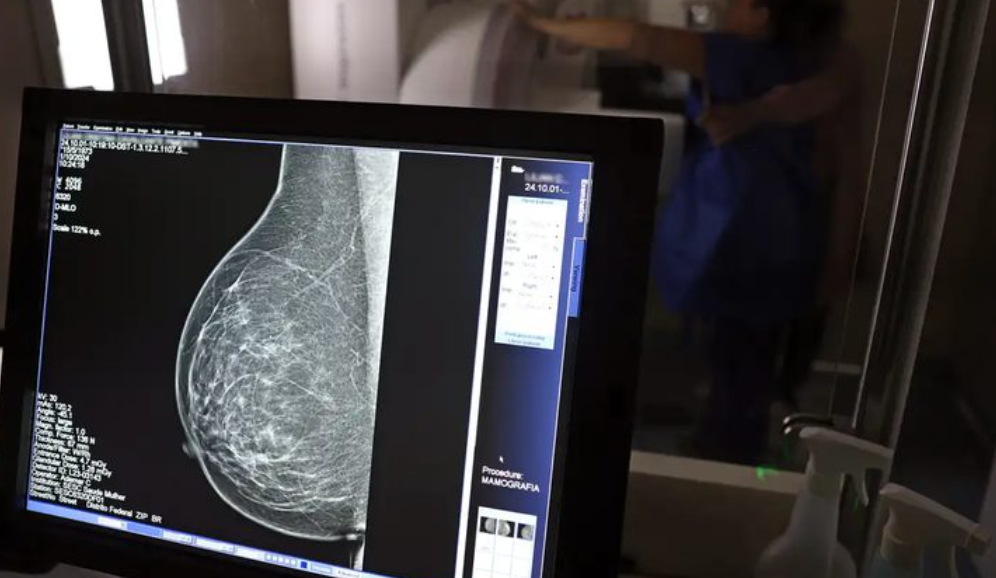

Descobrir o câncer de mama no início pode mudar destinos. Mais do que estatísticas, significa dar às pessoas a chance de seguir vivendo suas histórias. Neste Outubro Rosa, a Empresa Brasileira de Serviços Hospitalares ( Ebserh ), que administra 45 hospitais universitários federais, adere às novas recomendações do Ministério da Saúde. A partir de agora, quem tem entre 40 e 49 anos também terá acesso à mamografia pelo Sistema Único de Saúde (SUS).

Até então, o rastreamento era indicado a partir dos 50 anos. A atualização foi definida porque, segundo o Ministério da Saúde, a faixa etária dos 40 aos 49 anos concentra aproximadamente 23% dos casos de câncer de mama no Brasil. Além disso, houve ampliação da idade máxima para o exame: se antes era recomendado até os 69 anos, agora se estende até os 74 anos. Na Rede Ebserh , 24 hospitais ofertam mamografia. Somente no ano de 2024 , foram realizados mais de 54 mil exames.

O mastologista do Hospital de Clínicas da Universidade Federal de Uberlândia (HC-UFU), Donizete Willian Santos, afirma que “o diagnóstico precoce, principalmente com o rastreamento mamográfico, pode diminuir a mortalidade pelo câncer de mama em até 40% quando iniciado aos 40 anos na população de baixo risco. Além disso, reduz a necessidade de quimioterapia e o tempo em terapias complementares, como o bloqueio hormonal”.

Para o especialista, o autoconhecimento do corpo continua sendo um aliado importante. No Brasil, apenas 37% das mulheres em idade alvo realizam a mamografia, enquanto a recomendação da Organização Mundial da Saúde (OMS) é de 70%. “Embora o autoexame não diminua a mortalidade, ele conscientiza a mulher sobre a necessidade de realizar a mamografia e pode levá-la a procurar o serviço de saúde mais cedo, melhorando muito os resultados oncológicos”, explica.